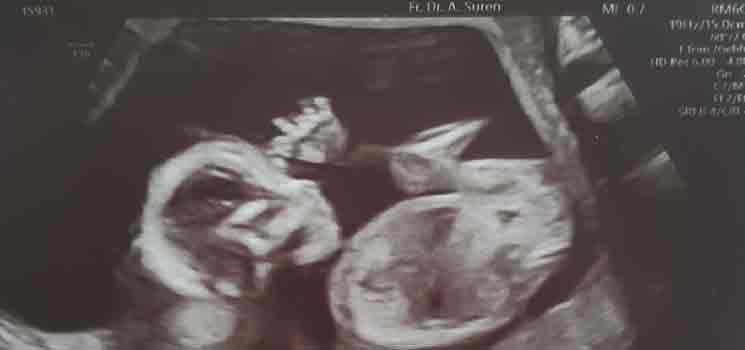

Meine neue Frauenärztin - Tagebücher aus der Schwangerschaft von Leandra aus Lübeck